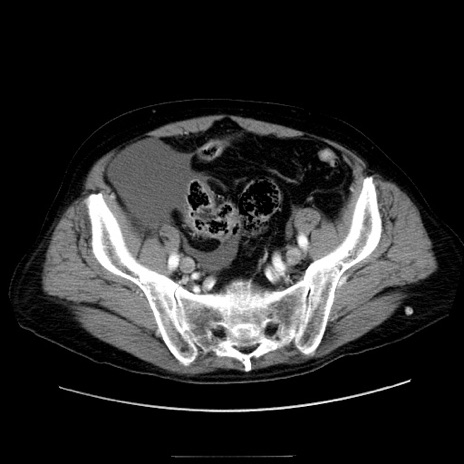

症例30(横断像)

【症例】80歳代男性

【主訴】臍周囲痛

【現病歴】約6時間前から臍下部痛が出現。次第に腹部膨隆・背部痛も生じてきたため来院。背部痛の場所は変化しない。

【身体所見】意識清明、BT 36.3℃、BP  131/87mmHg、P 87bpm、SpO2 100%(RA)、臍周囲自発痛・圧痛あり、反跳痛なし、自発痛部位に一致して板状硬あり、腹部膨隆、腸雑音減弱、CVA tenderness両側陰性。